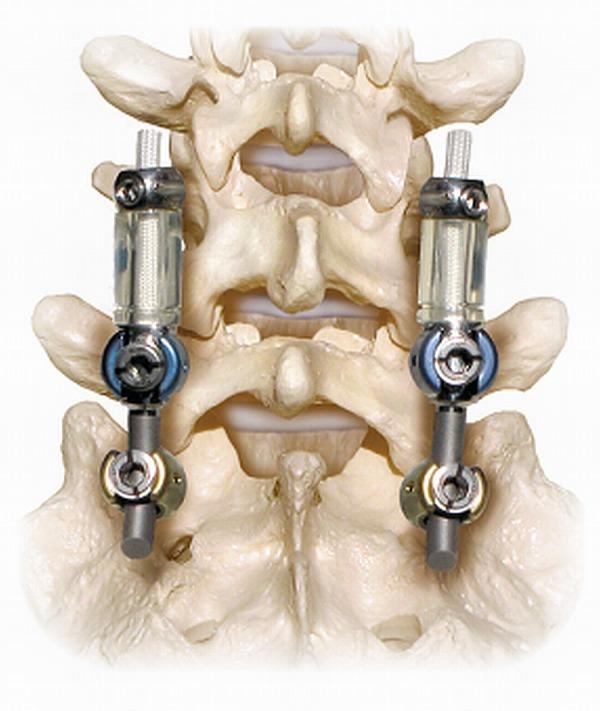

A clinical cohort investigation was conducted of 66 consecutive patients (31 female, 35 male; mean age: 53 years, range: 25 - 76 years) who underwent posterior lumbar instrumentation with the Dynesys Transition Optima (DTO) implant (Zimmer-Biomet Spine, Warsaw, IN) hybrid dynamic stabilization and fusion system over a 10-year period. The median length of follow-up was five years. DTO consists of pedicle screw fixation coupled to a rigid rod as well as a flexible longitudinal connecting system. All patients had symptoms of back pain and neurogenic claudication refractory to non-surgical treatment. Patients underwent lumbar arthrodesis surgery in which the hybrid system was used for stabilization instead of arthrodesis of the stenotic adjacent level.

对连续66例患者(31例女性,35例男性;平均年龄:53岁,范围:25 - 76岁)进行了一项临床队列研究,这些患者在10年期间接受了使用Dynesys Transition Optima(DTO)植入物(捷迈邦美脊柱公司,印第安纳州华沙)混合动态稳定与融合系统的后路腰椎内固定术。随访时间中位数为5年。DTO包括与刚性杆相连的椎弓根螺钉固定以及柔性纵向连接系统。所有患者均有背痛和神经源性间歇性跛行症状,非手术治疗无效。患者接受了腰椎融合手术,其中使用混合系统进行稳定,而非对狭窄的相邻节段进行融合。